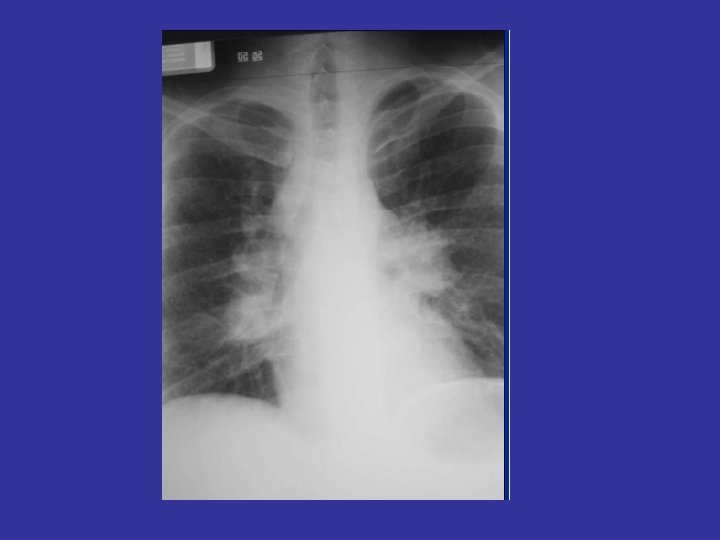

Beware of tunnel vision

How do you look at chest x ray? Avoid tunnel vision